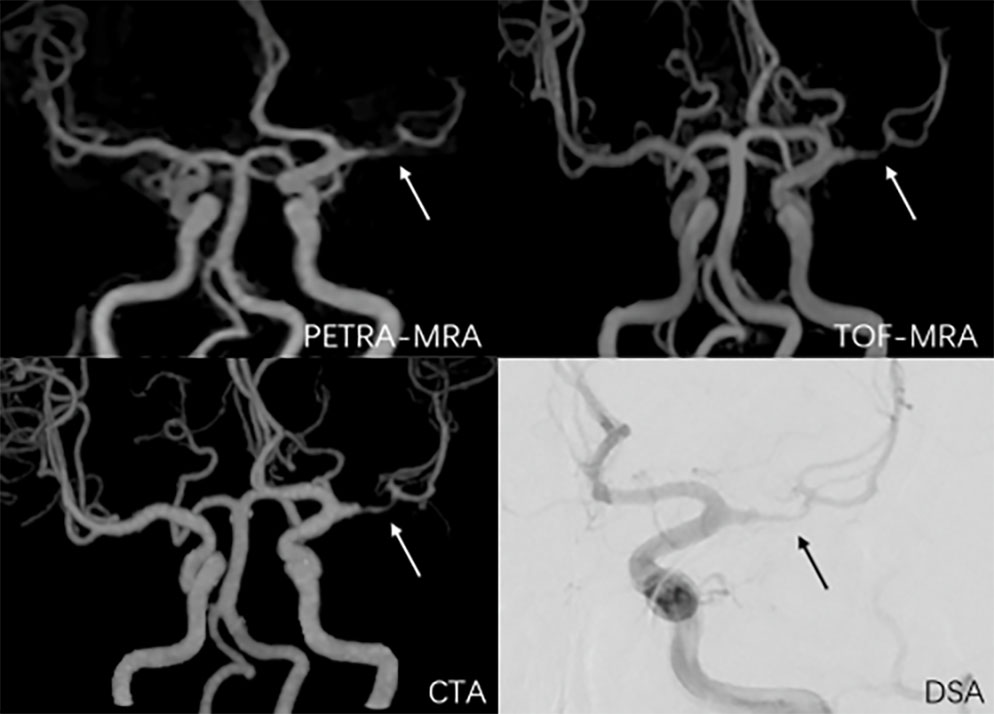

The inter-reader agreement for all the four imaging methods were excellent (ICCs > 0.80). PETRA-MRA, TOF-MRA, and CTA showed high image quality without any significant differences (P = 0.69) (Figure 1). Compared with DSA, PETRA-MRA was more consistent than TOF-MRA and CTA in measuring the degree of stenosis and the lesion length (Figure 2, 3). TOF-MRA and CTA significantly overestimated the degree of stenosis compared to the DSA (P <0.05 for both). However, PETRA-MRA did not overestimate the degree of stenosis compared to the DSA (P = 0.63).

Figure 1. Representative PETRA-MRA, TOF-MRA, CTA, and DSA images. The arrow denotes stenosis.